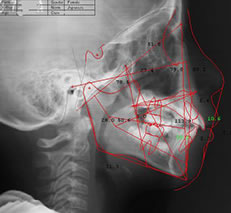

セファロ

セファロ」はレントゲンの一種です。普通のレントゲンが歯全体や上下のあごの画像を撮るのに対し、セファロは頭部全体を正面と横から撮影できます。

歯をどのように動かすか、また実際にどのように動いたかをより詳しく数値的に把握できます。

ドルフィンシステム

ドルフィンシステム」は、治療前の診断に必要なお顔のデータ分析だけでなく、術前・術後の歯や顎骨の変化を精密に分析することができる装置です。

歯科医師の「経験」と「勘」だけではなく、精密機器を活用することでより診断の質が高まります。